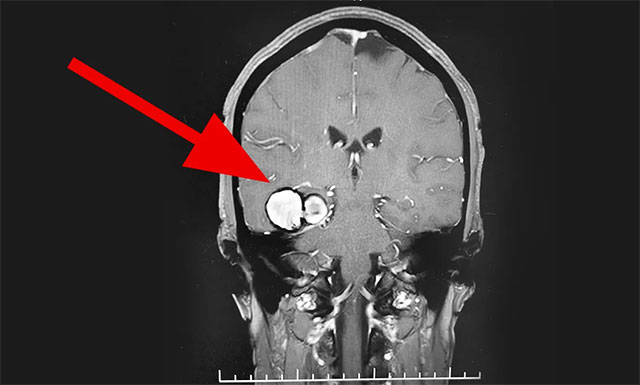

入院后,行MR头颅MRI平扫+增强+DWI+MRA显示,右侧颞叶见一团块状异常信号影,大小为 2.2cm×3.6cm×3.5cm, T1WI 呈高信号为主、边缘低信号环绕,T2WI、FLAIR及DWI高、低混杂信号、周边环状低信号,病周未见明显水肿带;增强后病灶未见明显强化征象。考虑患者有反复出血表现,为鉴别诊断,行全脑血管造影术示大动脉硬化,内膜毛糙,余血管未见明显异常。

▲ MR显示“血管瘤”位于右侧颞叶